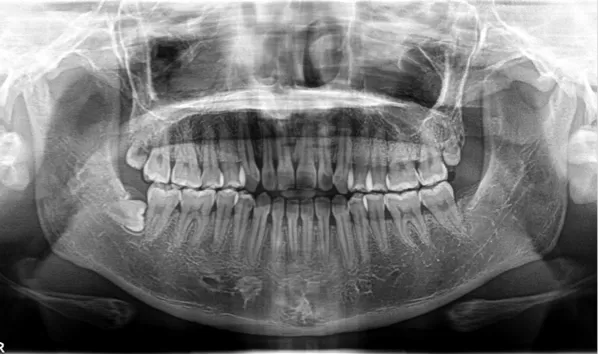

Rayons X avant le traitement

[Radiographie panoramique/Céphalogramme latéral]